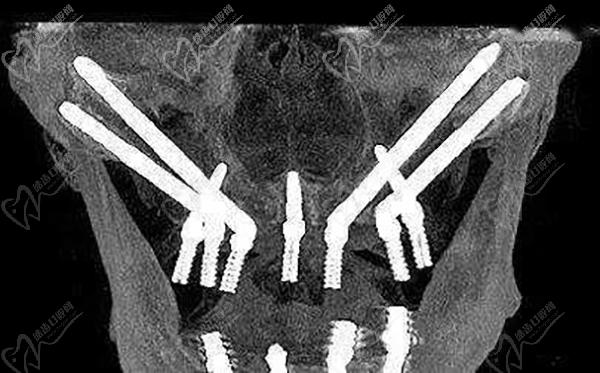

穿顴種植手術(shù),是通過將兩顆超長(zhǎng)植體斜植入顴骨來獲得超高的固位成效,然后在前牙區(qū)在垂直植入2-3顆普通植體,對(duì)于頜骨吸收情況比較重的牙友可以使用四顆穿顴種植體。穩(wěn)定性非常強(qiáng),是即刻種植修復(fù)技術(shù),大大縮短了種植牙時(shí)間,避免了大量植骨帶來的愈合等待期和風(fēng)險(xiǎn)。

在做穿顴種植手術(shù)的時(shí)候,因?yàn)橛袃深w植體斜插入顴骨貫穿面部神經(jīng)和血管區(qū),所以,需要在術(shù)前進(jìn)行詳細(xì)的CBCT頜面檢查,提取上頜竇等影響數(shù)據(jù)來確定非常精密的植入方案,來避免損傷神經(jīng)。大家做穿顴種植手術(shù)的時(shí)候切記要選擇正規(guī)醫(yī)院。

醫(yī)生要詳細(xì)了解術(shù)區(qū)的臨近動(dòng)脈、靜脈、神經(jīng),且植體長(zhǎng)度是常規(guī)植體的3-5倍長(zhǎng),起端極小的角度偏差都會(huì)導(dǎo)致末端的巨大偏離,造成手術(shù)失敗或損傷神經(jīng)的風(fēng)險(xiǎn),手術(shù)精細(xì)度非常高。